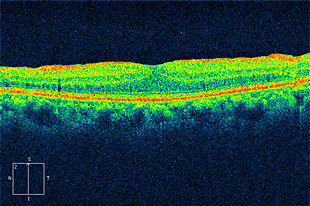

網膜静脈閉塞症

網膜静脈が詰まり、その先の静脈が拡張して蛇行し、眼底出血や浮腫が起きます。

出血や浮腫が黄斑部にかかると視力低下をきたします。

術前写真

術前 OCT

術後写真

術後 OCT